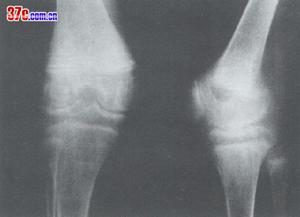

![]() | ![]() |

| 鐮狀細胞性貧血肘關節改變1 | 鐮狀細胞性貧血肘關節改變2 |